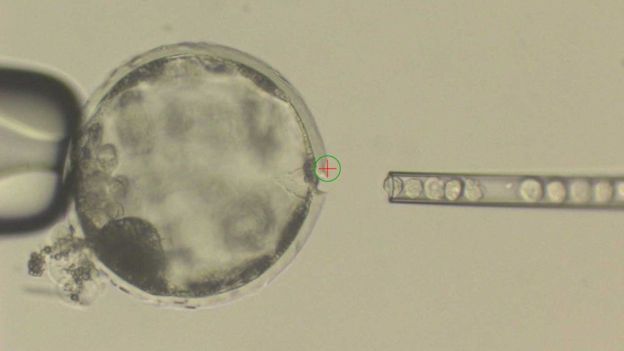

In a recent breakthrough study, scientists successfully created human-pig embryos. They were carried by adult pigs for about 4 weeks and then removed and analysed. The embryos contained only 0.001% of human cells, but enough to give this new study a promising start.

This new method, the creation of what is scientifically known as chimera – an organism containing genetic codes of two or more different species – seems to be the future. The idea is to insert human stem cells into pig embryos and get them to develop into adult creatures which would mostly be of pig nature, but having developed some human organs. They will potentially be more easily accepted when transplanted into human bodies and would even possibly eliminate the need for anti-rejection medication.